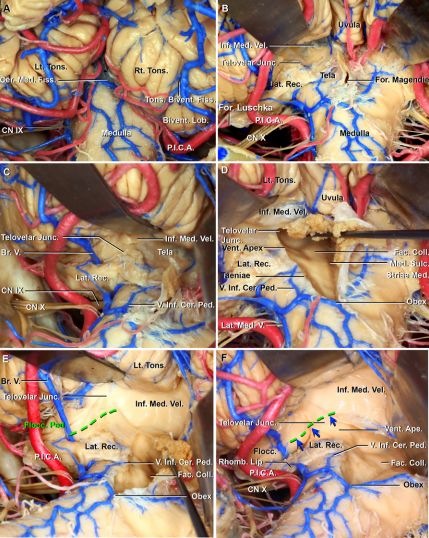

图1. A.外侧隐窝的毗邻关系(后面观);小脑中脚水平去掉右侧小脑半球,外侧隐窝由第四脑室外侧部组成。通过Luschka孔(第四脑室外侧孔)与小脑桥脑池相连,外侧隐窝分为延髓段和脑池段;B.外侧隐窝周围结构解剖和测量(表1);C.外侧隐窝周围手术入路,经小脑延髓裂外侧和内侧入路可以广泛的暴露外侧隐窝和小脑绒球脚,内外侧两种同时入路可以暴露外侧隐窝后下部(红线)。从脑干腹侧小脑绒球脚(绿色区域)处进入外侧隐窝是处理桥脑下部病变的最佳选择。橙色区域表示脑干腹侧蜗神经核。

枕下后正中入路时,打开延髓-扁桃体和蚓垂-扁桃体之间的间隙,可广泛暴露外侧隐窝(图5A、B)。当需要大范围暴露外侧隐窝时,在小脑延髓裂充分分离的前提下,作者偏好从对侧放置显微镜(图5C)。在分离过程中,注意保护PICA及其分支。因为小脑下脚静脉沿四脑室下外侧缘走行,这些静脉是袋状结构、附着于延髓的脉络组织及到达外侧隐窝Luschka孔(图5B-D)。分离膜髓帆交界和脉络膜带,打开外侧隐窝,暴露四脑室底部(图5D)。髓纹由稍白的纤维束组成,呈水平进入外侧隐窝。即使小脑延髓池有低位颅神经,从中线处也可以充分暴露(图5E、F)。

图5. 小脑延髓裂内侧入路。A.枕下后正中入路后面观,小脑延髓裂附着于扁桃体;扁桃体二腹裂是扁桃体和二腹叶之间的间隙,延髓扁桃体间隙位于延髓和扁桃体之间;B.牵开双侧扁桃体,打开小脑延髓池,暴露外侧隐窝段和膜髓帆交界;蚓垂扁桃体间隙位于蚓垂和扁桃体之间;C.内下位观,暴露四脑室和外侧隐窝外侧部,可见桥静脉走行于外侧隐窝;D.后面观,向上分离脉络膜带直至膜髓帆交界处,暴露进入外侧隐窝的延髓段、面神经丘、内侧沟和四脑室底部的髓纹;E.暴露延髓段后内下位观。在外侧隐窝外端,下髓帆形成绒球脚,进入绒球。绿色虚线表示绒球脚和假设进入桥脑的安全切口。

切除枕骨大孔外侧骨质后,经髁窝入路,打开小脑延髓裂暴露脑池和外侧隐窝延髓段(图6A、B)。采用此后下入路,可以更大范围的显露同侧外侧隐窝和内侧沟周围结构,而小脑延髓裂充分分离则可以更轻柔的牵开小脑。注意切勿损伤外侧隐窝腹侧上部的小脑延髓裂静脉(图6C、D)。打开外侧隐窝,切开膜髓帆交界或一步一步的分离脑池至外侧隐窝的延髓段(图6E)。此外,切开脉络裂带至第四脑室正中孔暴露同侧整个四脑室底部,包括面神经丘(图6F)。

图6. 小脑延髓裂外侧入路。A.左侧枕下开颅,从髁窝上方至下方遮挡髁管显露小脑延髓池和低位颅神经;B.从硬膜外钻孔和切除髁窝,避开位于舌下神经管上方的静脉结节;C.四脑室外侧部的外侧后下观。牵开左侧扁桃体后,暴露外侧隐窝脑池段、部分延髓段、菱唇和低位颅神经;D.分离小脑延髓裂后,很容易抬起扁桃体暴露部分外侧隐窝脑池段和延髓段,可见小脑延髓裂静脉和小脑下脚静脉走行于外侧隐窝周围;E.分离膜髓帆交界后,暴露整个外侧隐窝,蓝色小箭头表示附着于下髓帆至绒球背侧部的外侧隐窝;绿色虚线表示绒球脚和假定进入桥脑的安全切口;F.移除脉络丛后的放大观,暴露外侧隐窝脑池段和延髓段,背侧蜗神经位于绒球脚尾部。